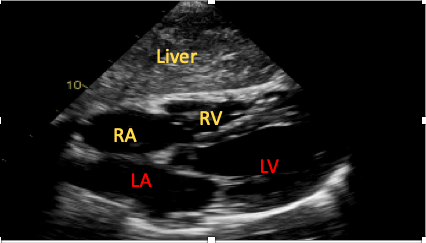

Subcostal Four-Chamber View (Coronal Plane)

The SC four-chamber view is achieved by placing the transducer under the patient’s xiphisternum, with the marker towards the patient’s left and the transducer held as flat against the patient’s abdominal wall as possible (Figure 5). Novice scanners commonly fail to obtain sufficient images secondary to insufficient pressure application or because the transducer is held too vertically.15

Figure 5. The subcostal four-chamber view.

RA=right atrium, RV=right ventricle, LA=left atrium, LV=left ventricle